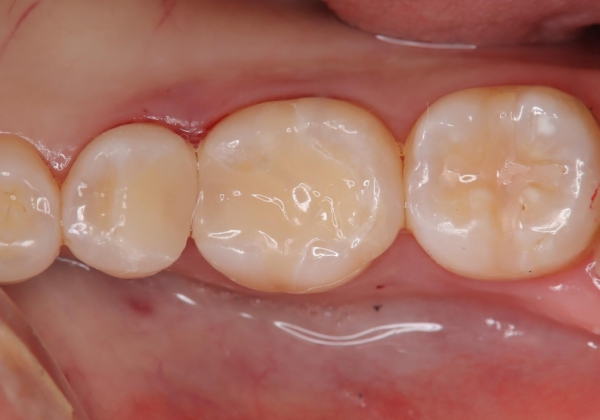

- 虫歯が複数個所あり、来院回数を抑えて治療をしたいという患者様でした。当院では光学スキャナ・ミリングマシンを設置しておりますので、1日でセラミック修復治療を完了させました。術後も良好な経過をたどっています。

メタル修復物の場合X線を通さない性質があり、レントゲン写真を撮るとメタルの部分が真っ白に写ってしまうため、詰め物の下の虫歯が分かりにくくなってしまうというデメリットがあります。これに対し、今回の即日セラミック修復に使用したMarkⅡという材料は、レントゲン写真からもわかる通り歯の一番外側の部分(エナメル質)と同程度のX線透過性を持ちます。そのため装着後も定期的なメンテナンスにより虫歯の再発を早期に発見できるメリットがあります。